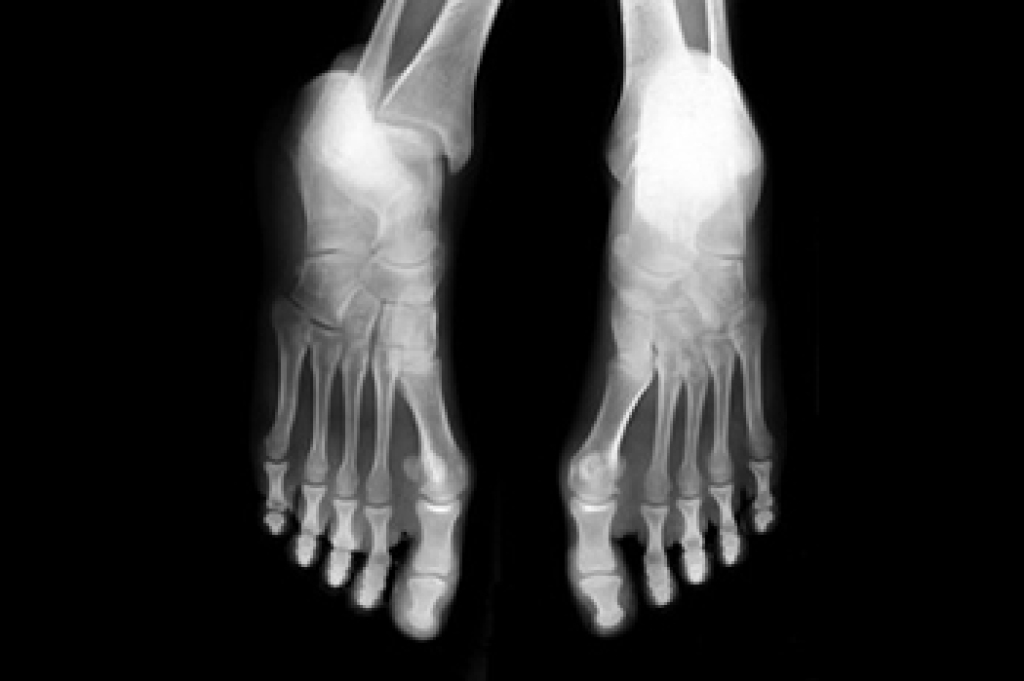

In many cases the cause of toe pain is obvious, but in others, a podiatrist may want to use more advanced methods to determine the problem. These can range from simple visual inspections and sensation tests to X-rays and MRI scans. Prior medical history, family medical history, and any recent physical traumatic events will all be taken into consideration for a proper diagnosis.